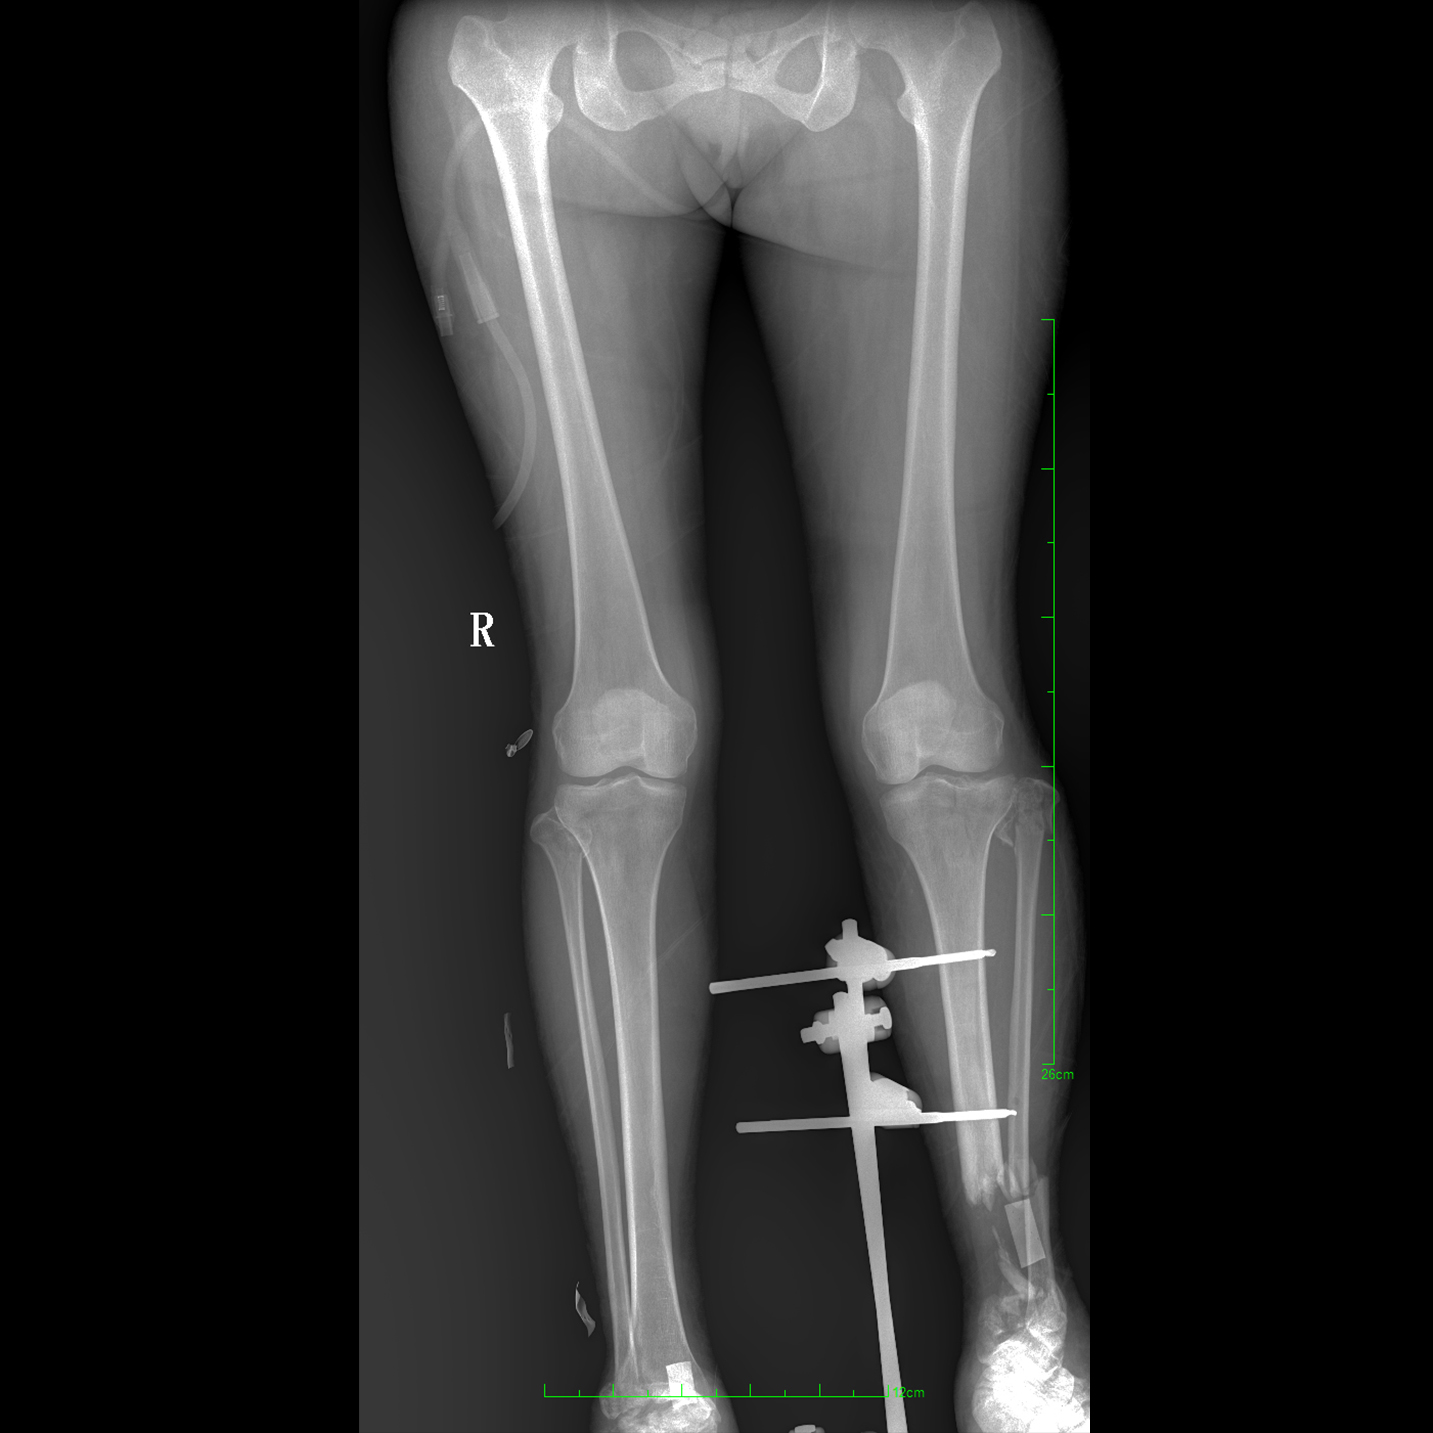

支持全脊柱摄影、双下肢摄影、脊髓造影、复杂创伤、人工关节置换、关节损伤的修复重建等大视野临床应用

全脊柱一次成像 不拼接

17"*34"有效视野,一次成像不拼接。相较于多张摄影再软件拼接的DR设备,PLX8600解决了拼接图像存在密度不均匀,拼接处图像配准和放大效应等问题,给临床带来了大视野影像解决方案,可一次性覆盖全脊柱或双下肢影像。

Clinical picture

临床图片